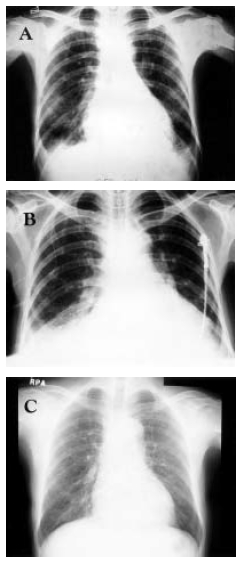

A 50-year-old woman was admitted due to high fever and progressive dyspnea for 20 days. For ten years, she suffered from arthritis which was treated irregularly, without specific evaluation, at a private clinic. Eleven days before, she visited another hospital because of fever, cough, sputum and dyspnea with mild pleuritic chest pain. She was managed under the impression of tuberculous pleurisy, but she did not improve with anti-tuberculous medication. A chest radiography showed right pleural effusion with bilateral pulmonary infiltrations (Figure 1A). Cytology of pleural fluid revealed mesothelial cells, histiocytes and neutrophils. Serum creatinine level was 2.2 mg/dL. She was brought to this hospital for further evaluation and management.

A chest radiograph showed pneumonic infiltrations in both lower lung fields with pleural effusion (Figure 1B). Laboratory studies revealed hemoglobin of 8.5 g/dL, hematocrit of 24%, white blood cell count of 3900/mm3 (13% of band form, 85% of segment form), platelet count of 148,000/mm3 and ESR of 72 mm/hr. Serum creatinine was 2.5 mg/dL, protein was 7.2 g/dL and albumin was 2.5 g/dL. Urinalysis showed proteinuria (+2) and hematuria (+4). Antinuclear antibody was positive (1/640, speckled pattern), but anti-DNA antibody was negative. Tests for anti-Ro, anti-La and anti-RNP antibodies were positive. The level of C3 and C4 were decreased to 25 mg/dL (normal 45–100 mg/dL) and 9 mg/dL (normal 10–40 mg/dL), respectively. C-reactive protein was 7.2 mg/dL (normal <0.5) and rheumatoid factor was 52 IU/mL (normal <20). Direct Coombs’ test was positive, but indirect Coombs’ test was negative.

The patient was treated with prednisolone of 1 mg/kg/day for one month. But, she had no improvement on radiologic finding and showed generalized edema as an adverse effect of steroids. With prednisolone tapering, she was also added oral cyclophosphamide 50 mg/day. Following this therapy, her condition significantly improved in subjective symptoms, physical signs and objective pulmonary function and radiologic findings (Figure 1C).